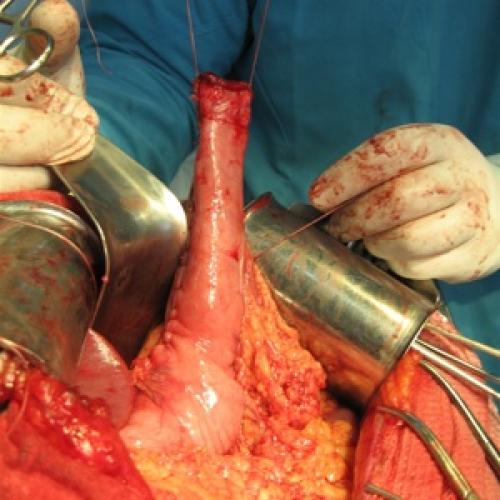

В настоящей статье представлены результаты оперативного лечения 114 пациентов, страдающих гастродуоденальными язвами, осложненными суб- и декомпенсированным…

Roux-реконструкция как метод хирургической коррекции постгастрорезекционных…

В работе обоснована целесообразность использования Roux-реконструкции верхних отделов желудочно-кишечного тракта при лечении постгастрорезекционных и постгастрэктомических…

Профилактика регургитационных осложнений при дистальной резекции пищевода

В работе представлен анализ результатов клинического применения эзофагогастропластики с формированием антирефлюксного пищеводно-желудочного анастомоза…